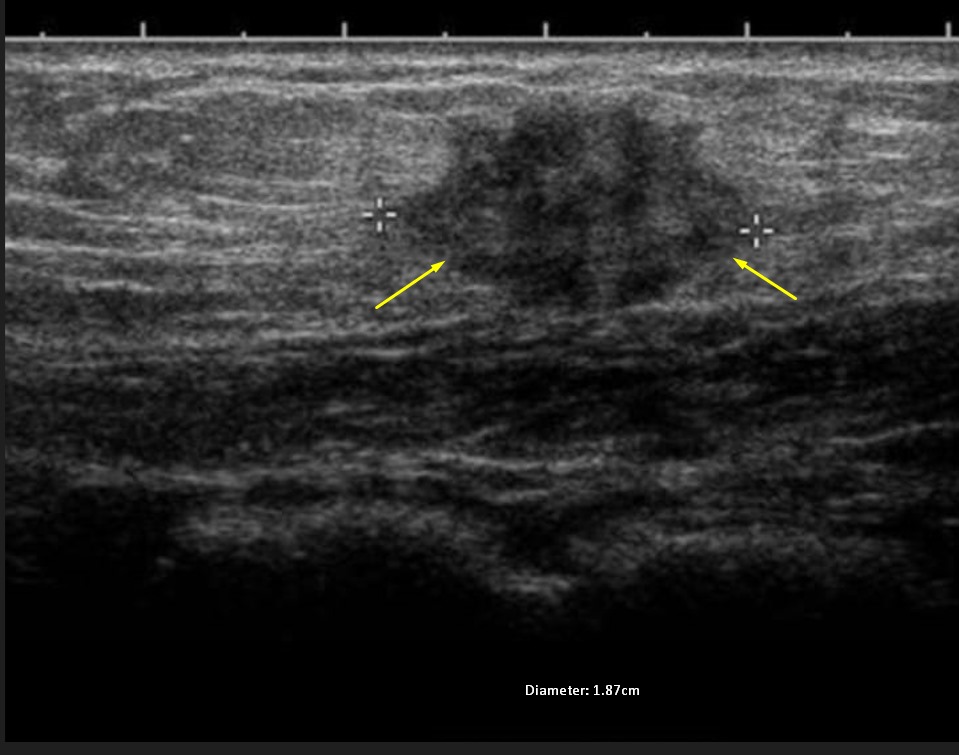

Abdominal wall endometrioma was detected in the physical and radiological examination (superficial ultrasound) (Fig. 4) of 204 patients who presented to our general surgery clinic due to complaints of swelling and pain in the abdominal wall. Masses were on the right side of the incision line in 160 (78.4%) patients. In the superficial ultrasound of the patients, AWE was above the rectus fascia in 110 patients and at the level of the rectus abdominis fascia in 94 patients. In only 1 patient, the mass was localized outside the cesarean scar site. Wide excision was performed under general anesthesia in 204 patients. The pathology of 203 patients was evaluated as compatible with endometrioma (Fig. 5). The pathology result of the remaining 1 patient was compatible with desmoid tumor. Postoperatively, only 1 patient had a hematoma. She recovered with conservative treatment. Repeat pregnancy was planned in 204 patients after an average of 2.5 years. AWE recurred in 9 of the patients in Group I during the follow-up period (4.4%). These patients underwent repeat total excision.

Fig. 4. Superficial ultrasonography of abdominal wall endometrioma.

Ultrasonography is the first-line diagnostic imaging method in the evaluation of abdominal wall abnormalities [21]. Three positions for abdominal wall endometrioma (AWE) have been identified based on its location relative to the rectus abdominis muscle: superficial placement (above the fascia of the rectus muscle), intermediate placement (at the level of the fascia of the rectus muscle), and deep placement (below the fascia of the rectus muscle) [22]. In our study, AWE localized under the muscle was not detected. On ultrasound, AWE appears as a heterogeneous hypoechoic mass with hemorrhagic and fibrous components present.